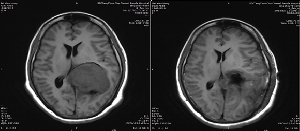

神經(jīng)外二科成功實(shí)施側(cè)腦室三角區(qū)巨大腦膜瘤全切術(shù)

8月2日,以續(xù)繼軍主任為首的神經(jīng)外二科團(tuán)隊(duì),精心設(shè)計(jì)手術(shù)方案以及圍手術(shù)期的管理,依托三博腦科醫(yī)院合作平臺(tái),在專家的指導(dǎo)下術(shù)中選擇無功能區(qū)皮層造瘺,采用瘤體中心減壓